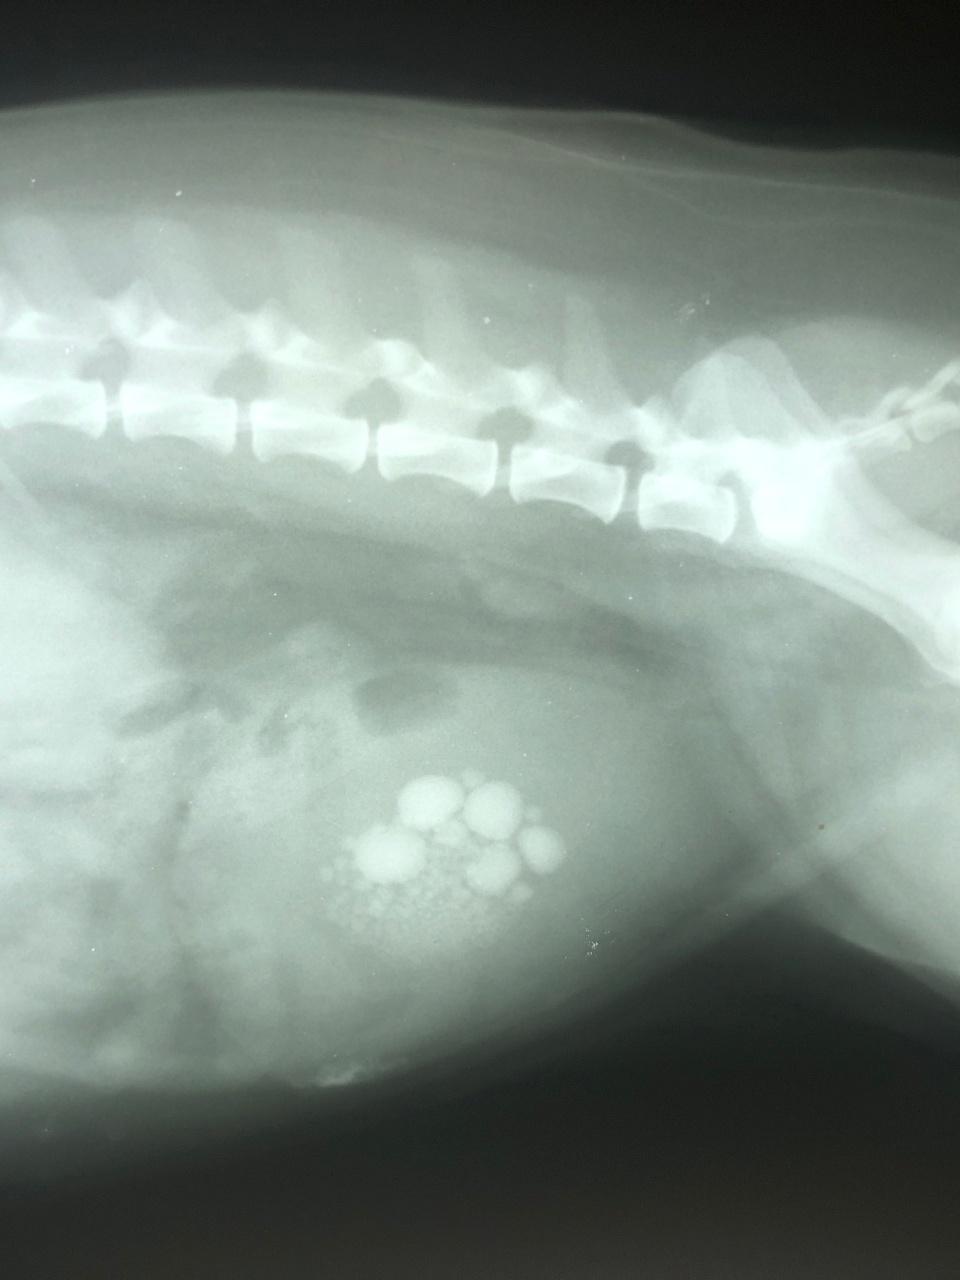

While bladder stones are made up of urinary crystals, they are not the same thing. Dogs can have crystals in their urine but no stones. Stones are visible without a microscope and will usually show up on an X-ray or ultrasound. Crystals are microscopic, and not visible to the naked eye.

The best way to check for stones is with a combination of radiography and ultrasonography. Some stones will show up on X-rays, while others show up better on ultrasound.

Struvite and oxalate (the most common type of stones) are radiopaque, meaning they should show up on plain X-rays.